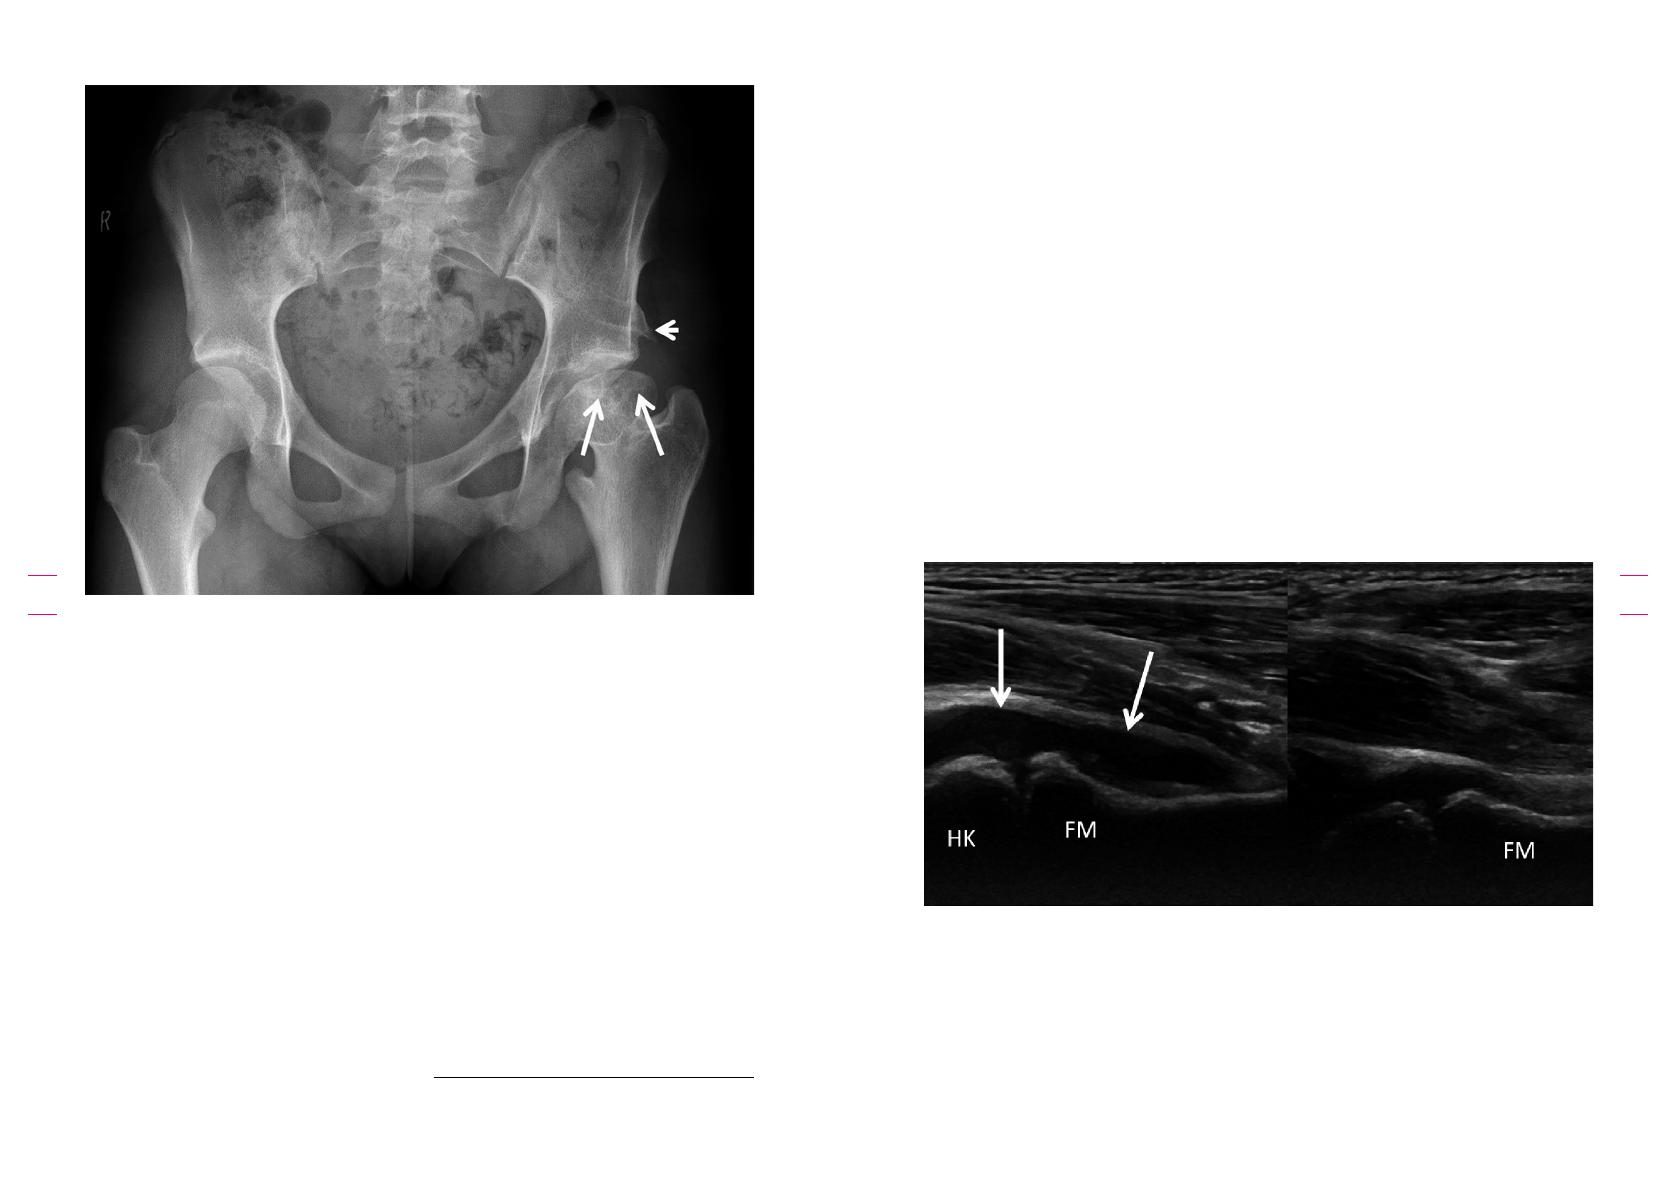

Figure 4: Arthrite septique: Garçon de 10 ans avec fièvre, boiterie et douleur de la hanche droite. La radiographie simple

n’a rien montré. L’échographie démontre un épanchement articulaire avec épaississement synovial. L’IRM, en l’occurrence en

coupes coronales pondérées après injection iv. de contraste (gadolinium), démontre clairement un épaississement avec prise

de contraste de la synoviale de la hanche droite et un épanchement évident.

Enfin, l’ACR considère que, pour l’enfant âgé de

0 à 5ans présentant une boiterie et des signes

cliniques d’infection, l’examen de premier choix

est l’échographie des hanches (score de perti-

nence: 9), suivi d’une radiographie en vue AP du

bassin (dose ecace: 0,03-0,3 mSv), à laquelle

elle attribue un score de pertinence de 8 (Fig.

4). L’IRM pelvienne, avec et/ou sans contraste,

est quant à elle dotée d’un score de pertinence

de 7, tandis que la scintigraphie osseuse et le CT,

qui sont recommandés lorsque l’IRM n’est pas

possible, sont dotés d’un score de pertinence

respectif de 5 et 4. Dans le contexte belge,

la présence de liquide dans l’articulation peut

éventuellement (en fonction de l’âge de l’enfant)

justifier la combinaison d’une échographie et

d’une aspiration échoguidée, qui pourra servir à

la réalisation d’une culture avec antibiogramme.